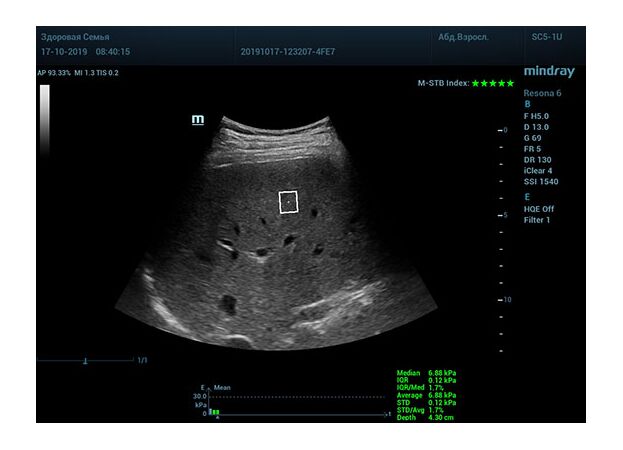

Что может дать ультразвуковое исследование печени помимо образований, гепатомегалии и цирроза? Диагностические системы, оснащенные функцией STQ (SoundTouchQuantification) имеют возможность регистрировать сдвиговые волны в паренхиме печени и оценить её эластичность. Такие возможности есть у систем серии Resona 6 и Resona 7 компании Mindray.

Датчик посылает ультразвуковую волну способную сжать участок паренхимы печени. В момент расправления тканей органа после сжатия, происходит образование поперечные волн. Для их регистрации, следом за волной сжатия, посылается регистрирующая волна, которая улавливает изменения скорости. Закономерность изменения скорости позволяет использовать модуль Юнга для оценки плотности ткани. Таким образом мы получаем аналог FibroScana’а, который упоминается в рекомендациях по диагностике и лечению жировой болезни печени, фиброза и цирроза. Разница в том, что теперь не нужно приобретать отдельный прибор. Все уже есть в ультразвуковой системе. Быстрее, дешевле, доступнее. Так же исчез пугающий пациента эффект «удара» типичный для фиброскана. Методика, в отличии от биопсии, не инвазивная и может применяться даже у детей.

Определение плотности печени. Не ошибся ли оператор при измерении эластических свойств печени? Для оценки критериев качества предусмотрен индекс MBT, который покажет насколько «твердой» была рука оператора и двигалась ли печень. При MBT 5* рука тверда и показатели достоверны. Для оценки качества результатов используется IQR индекс, отображающий колебания показателей в точке измерения при расчете медианы. Показатели при IQR <30% считаются приемлемыми. Техника сканирования через межреберные промежутки требует размещение окна интереса на несколько сантиметром ниже капсулы, для исключения эффекта реверберации. Установка ROI на паренхиму без захвата сосудов, для исключения погрешностей измерения.